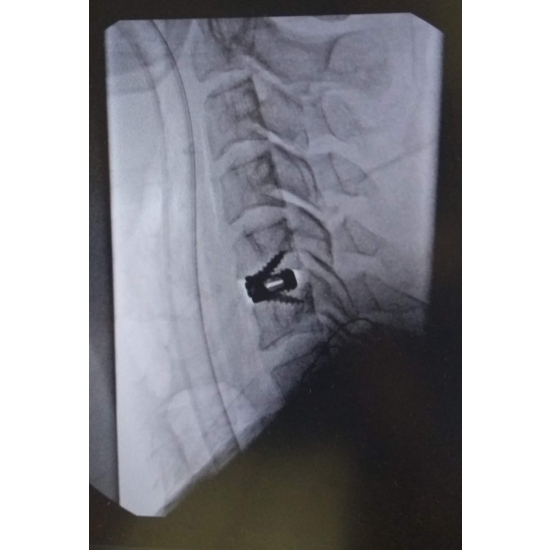

The treatment was an Anterior Cervical Discectomy and Fusion of C5-C6. Case Photo #2

The patient was taken to surgery for repair of the C5 lamina fracture approximately three months following the initial incident. Following surgery and physical therapy, he made a full recovery and gained back full strength in his right upper extremity and radiculopathy symptoms resolved.